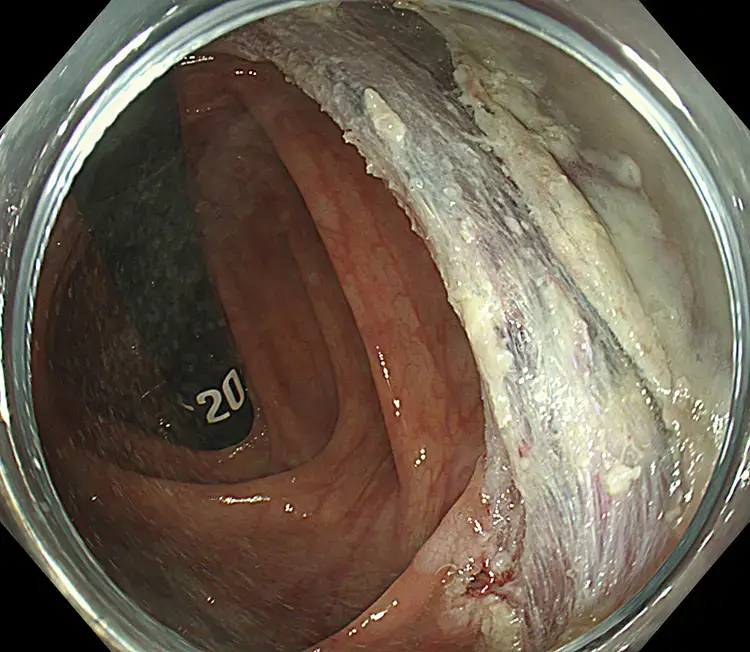

Endoscopic Mucosal Resection (EMR)

Endoscopic Mucosal Resection (EMR) is performed during colonoscopy. Fluid is gently injected beneath the polyp to lift it away from the bowel wall. A fine wire loop (snare) is then placed around the polyp and removed with a small electric current, which also seals blood vessels to reduce bleeding. Larger polyps may be removed in pieces. All removed tissue is collected and sent to the laboratory for analysis.